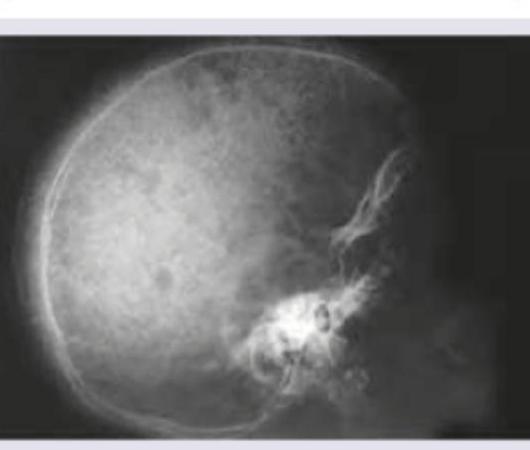

Explanation: **Explanation:** **Graves’ disease** is an autoimmune disorder characterized by the production of **Thyroid Stimulating Immunoglobulins (TSI)** [1]. These autoantibodies act as agonists to the TSH receptors on the thyroid gland, leading to unregulated synthesis and release of thyroid hormones ($T_3$ and $T_4$) [1]. This results in **Hyperthyroidism**, making Graves' disease the most common cause of thyrotoxicosis worldwide (accounting for 60-80% of cases) [2]. **Analysis of Options:** * **Option A (Hypothyroidism):** This is incorrect. The most common cause of hypothyroidism in iodine-sufficient areas is **Hashimoto’s Thyroiditis**, where antibodies (Anti-TPO) lead to glandular destruction rather than stimulation. * **Option C (Thyroiditis):** While Graves' is an autoimmune process, "thyroiditis" usually refers to inflammation leading to the leakage of stored hormones (e.g., De Quervain’s or Subacute thyroiditis). Graves' involves active overproduction, not just leakage. **High-Yield Clinical Pearls for NEET-PG:** * **The Classic Triad:** Hyperthyroidism (Goiter), Ophthalmopathy (Exophthalmos), and Dermopathy (Pretibial Myxedema) [1], [2]. * **Diagnosis:** Characterized by Low TSH, High Free $T_4$, and **diffuse increased uptake** on Radioactive Iodine Uptake (RAIU) scan [2]. * **Specific Marker:** TSH Receptor Antibodies (TRAb/TSI) are highly specific for Graves' [1]. * **Histology:** Look for "scalloping" of the colloid at the edges of follicular cells, indicating active hormone resorption.